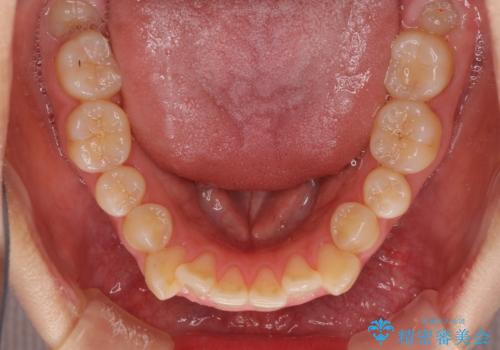

狭い歯列を拡大 拡大装置を併用したインビザライン矯正

- 八重歯と前歯のデコボコを気にして来院された患者様です。

八重歯の他に、上顎歯列を狭窄しているという問題点がありました。

また、八重歯により上顎奥歯が前方に位置しており、咬み合わせの改善も必要な状況でした。

インビザラインによる矯正治療を希望されたため、上顎歯列の側方拡大奥歯の遠心移動のための補助装置を併用し、その後はインビザラインにて行うこととしました。